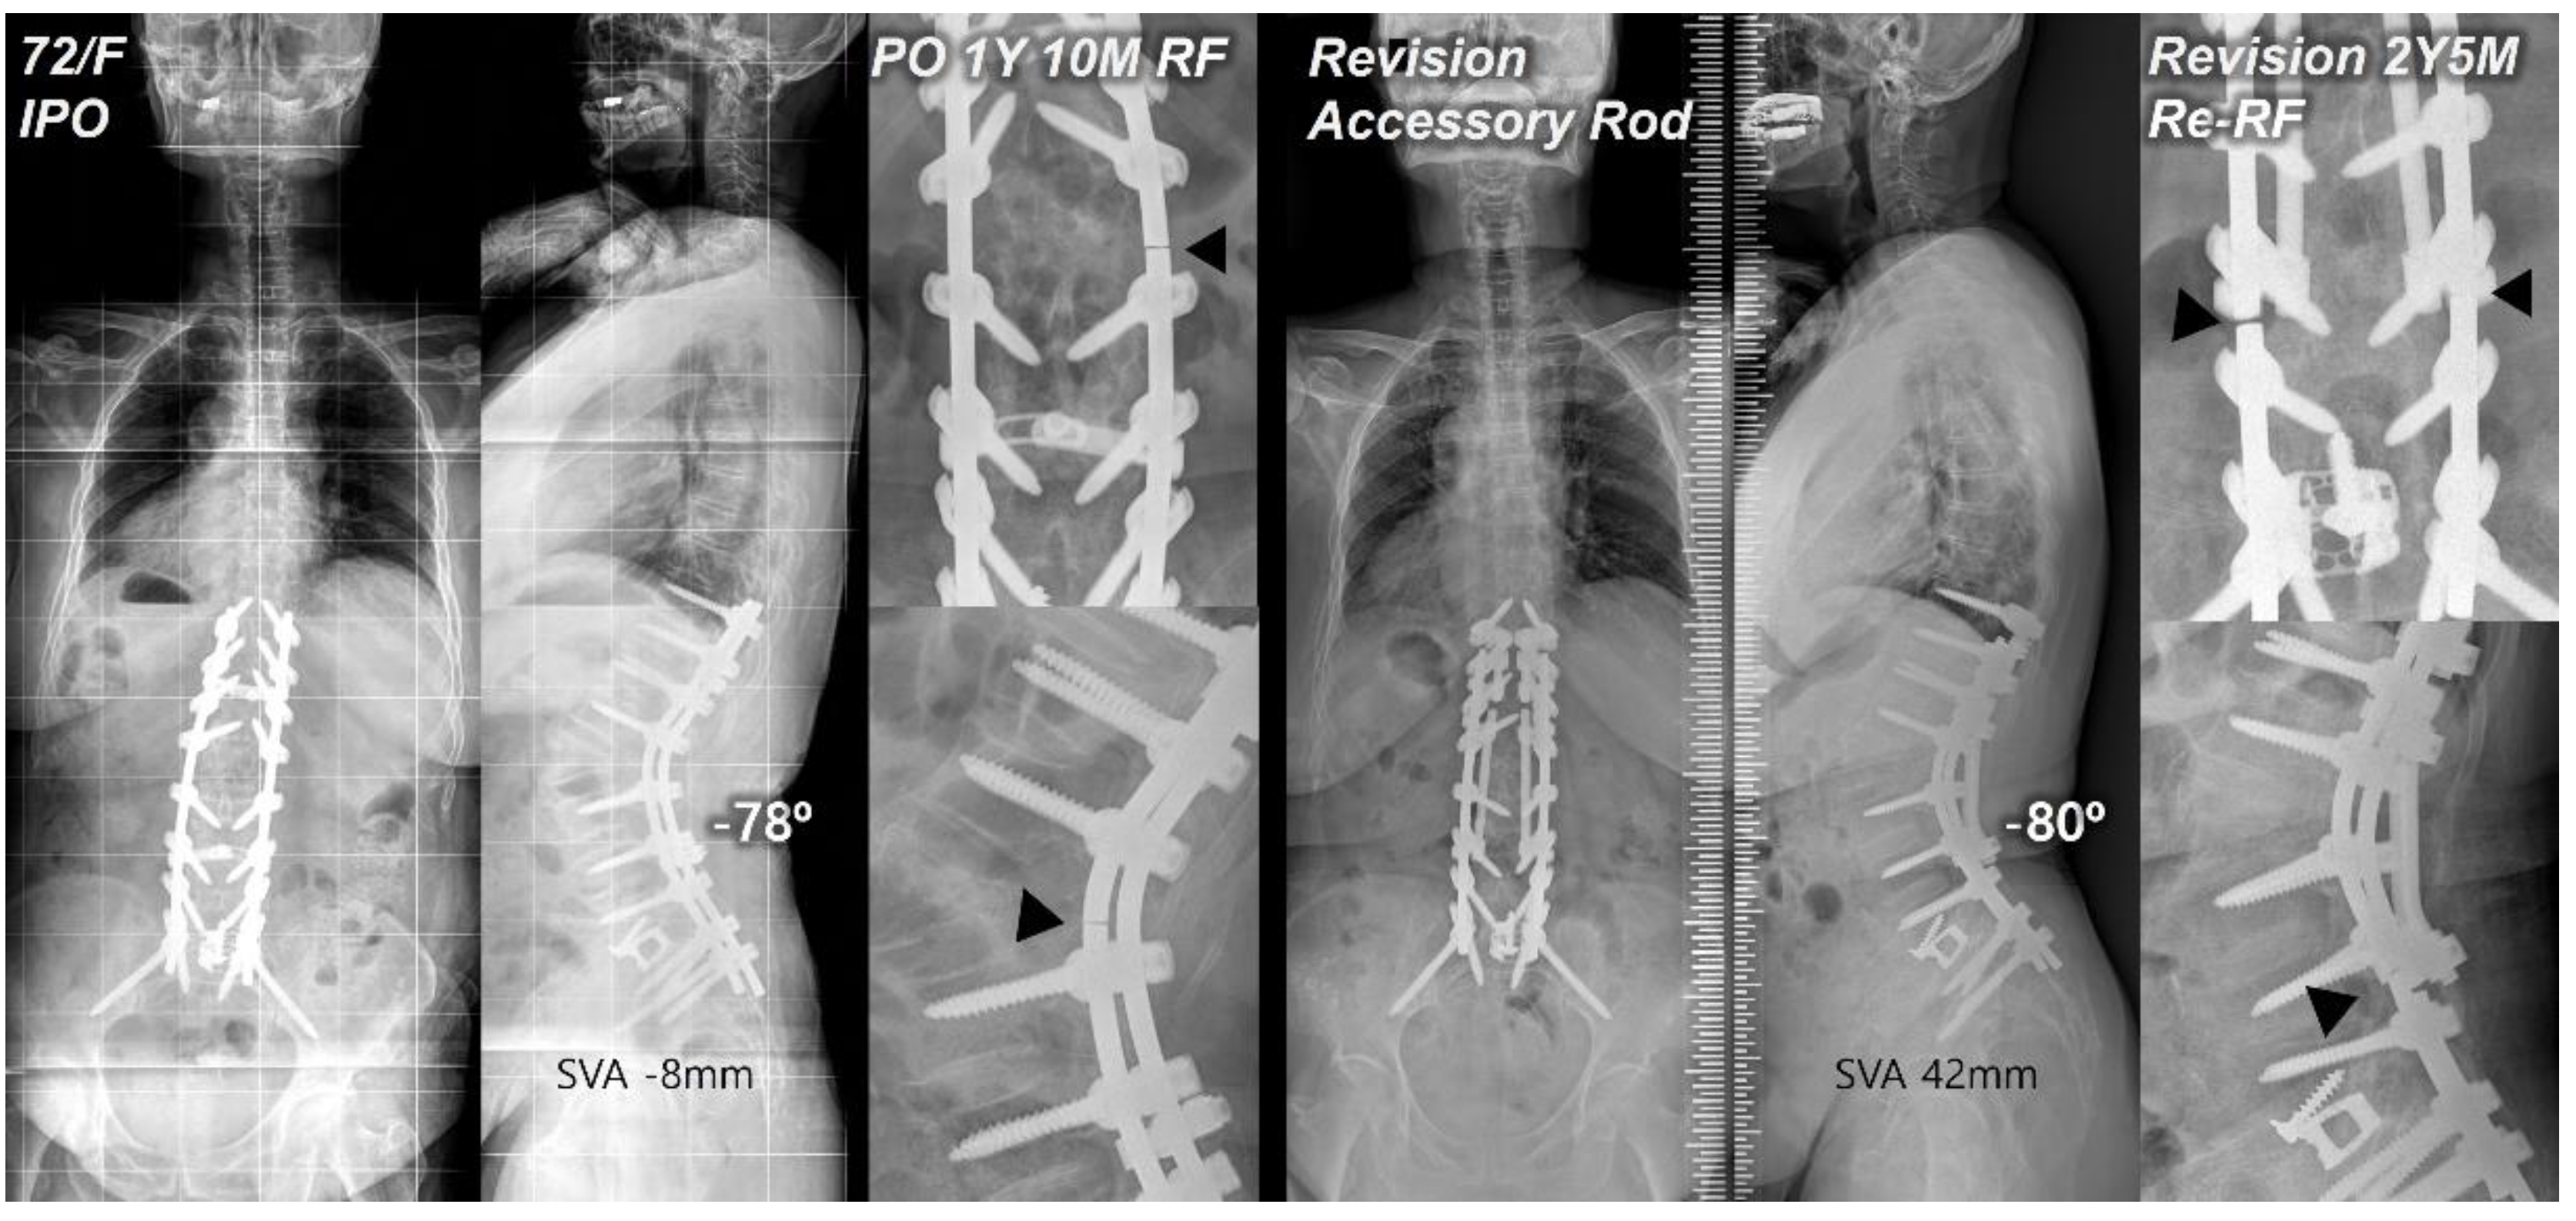

Figure 2. Postoperative standing radiographs of a 72-year-old female patient after T10-S1 posterior instrumentation with PSO on L2, and ALIF on L5-S1 with an optimal sagittal balance (SVA, -8 mm; TK, 27°; LL, -78°; PI, 60°; PT, 12°; SS, 48°). At 1 year and 10 months after primary deformity correction, RF (right rod) occurred at L2-3. At two years and 5 months following revision surgery with bilateral rod replacement and accessory rod integration, re-RF occurred at L4-5. Black triangles indicate sites of RF.

Posterior reinforcement at the PSO site with multiple-rod fixation for appropriate load distribution is a crucial preventive method for RF. Numerous finite element models have demonstrated the effectiveness of additional rods in reducing stress on the primary rods across the osteotomy site [22,23]. Several clinical studies also have reported that multiple-rod fixation reduced the occurrence of RF and increased the stability at the osteotomy site [3,9]. A biomechanical study by Scheer et al. [24] that analyzed revision strategies for RF in PSO reported that multiple-rod fixation could restore stiffness and prevent fatigue of revision constructs. Therefore, multiple-rod fixation should offer a proven biomechanical stability in revision for RF. However, RF can still occur even with reinforcement. In our study, re-RF occurred in one of 22 patients in the AR group. Interestingly, instead of occurring at the PSO site, it occurred just below each junction between the distal end of the AR and the primary rod (Figure 2). We believe that, in the application of multiple-rods, connecting the distal end of the AR to the previous instrumentation at the S1-2 area could potentially offer increased stability in conjunction with L5-S1 interbody fusion and sacropelvic fixation, but further studies are warranted.